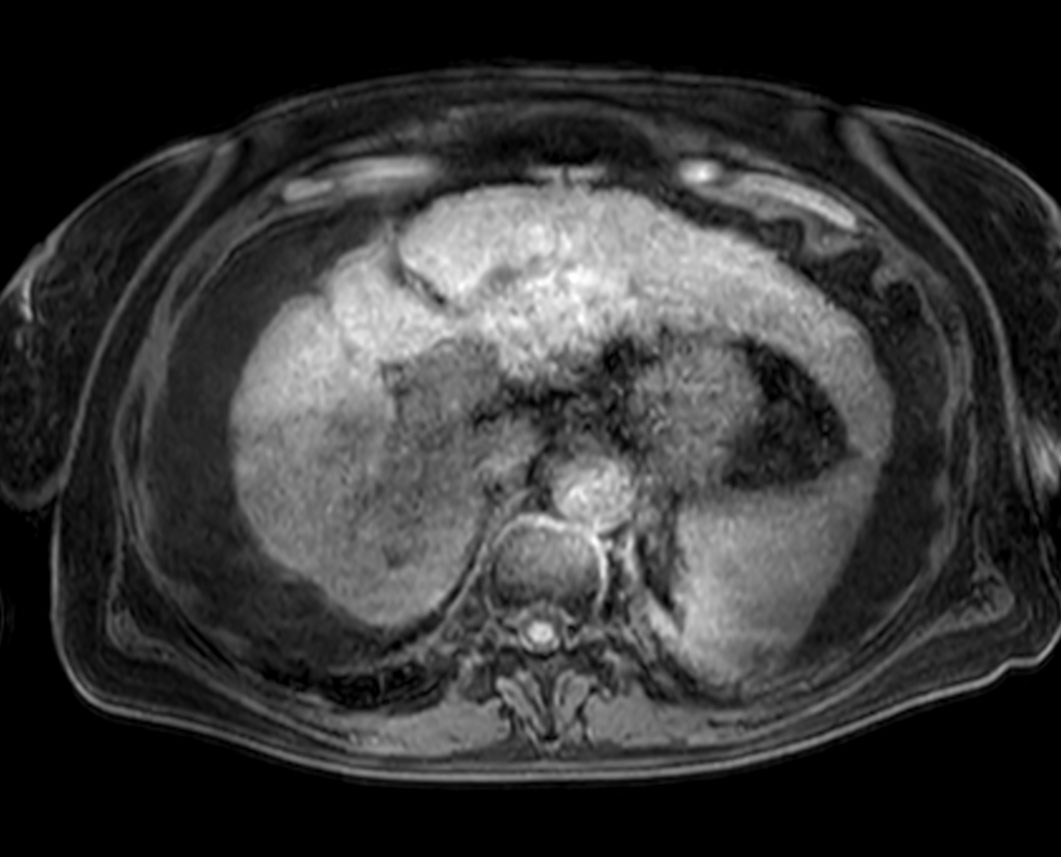

Axial Diffusion - b50